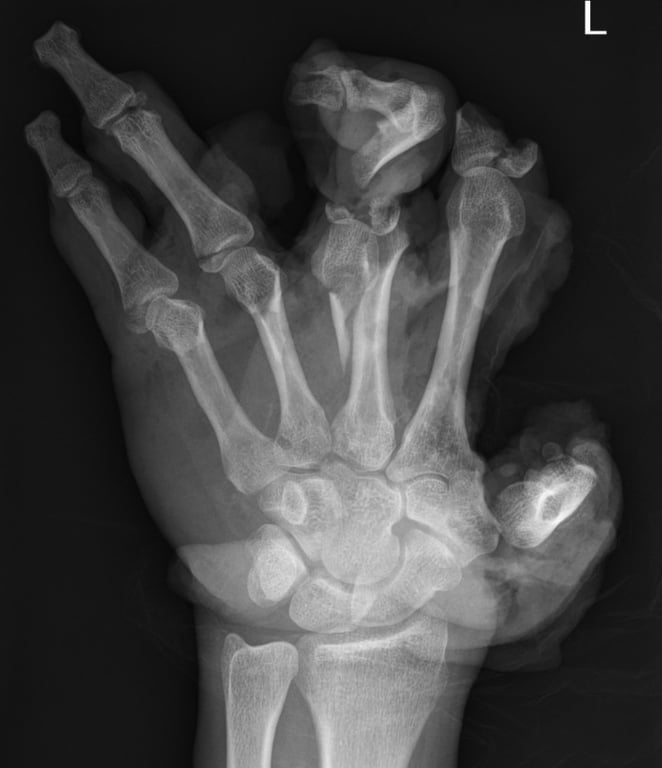

В 2019 році 22-річний Вардан Атанесян втратив ліве око через необережний запуск феєрверків. Сталося це на узбережжі близько опівночі. Хлопці купили салют на одному з одеських ринків. Першим запустити його вирішив саме Вардан. Але все пішло не за планом.

"Все було виконано правильно, за інструкцією: трубка дивилася вверх під невеликим кутом. Я запалював гніт запальничкою на відстані витягнутої руки, а потім швидко відбіг на безпечну відстань. Але салют не спрацював. Ми чекали 10 хвилин, але він так і не запустився. Тоді я підійшов до нього, нахилився над гнотом і в цей момент феєрверк вистрелив прямо мені в обличчя", – згадує цей страшний день 22-річний одесит.

А потім все як в тумані, каже Вардан Атанесян. Пам’ятає лише звук сирени "швидкої" і паніку людей навколо. Хлопець пережив кілька операцій, однак ліве око врятувати так і не вдалося.

"Мене госпіталізували з діагнозом “проникаюче поранення лівого ока”. Але постраждало й інше око. Його врятували. Я проходив тривале лікування. Треба було чекати, коли відновляться повіки та інші тканини обличчя. Але зараз я добре бачу на одне око. Замість другого – протез, естетику самої повіки відновити не вдалося. На обличчі залишилося кілька шрамів, але я вже звик до своєї нової зовнішності", – розповів Вардан Атанесян.